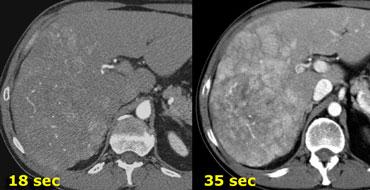

Các khối u tăng mạch sẽ ngấm thuốc tối ưu ở thời điểm 35 giây sau khi tiêm thuốc cản quang (thì động mạch muộn).

Khoảng thời gian này cần thiết để thuốc cản quang di chuyển từ tĩnh mạch ngoại vi đến động mạch gan và khuếch tán vào khối u gan.

Hình bên trái là một bệnh nhân được chụp hai thì động mạch ở thời điểm 18 và 35 giây.

Trong thì động mạch sớm, chúng ta thấy rõ các động mạch, nhưng chỉ thấy một số vùng ngấm thuốc không đều trong gan.

Trong thì động mạch muộn, chúng ta có thể xác định rõ ràng nhiều khối u.

Lưu ý rằng trong thì động mạch muộn phải có một phần ngấm thuốc của tĩnh mạch cửa.

Thì động mạch sớm chỉ cần thiết khi cần chụp động mạch đồ, ví dụ như bản đồ đường mạch cho nút hóa chất khối u gan.

Thời điểm chụp quan trọng, nhưng tốc độ tiêm thuốc cản quang cũng gần như quan trọng không kém.

Đối với chụp thì động mạch, kết quả tốt nhất đạt được với tốc độ tiêm 5ml/giây.

Có hai lý do giải thích cho sự ngấm thuốc tốt hơn này: ở tốc độ 5ml/giây, lượng thuốc cản quang đến gan nhiều hơn khi bắt đầu chụp và thuốc đến với nồng độ cao hơn.

Hình bên trái là một bệnh nhân xơ gan được chụp sau khi tiêm thuốc cản quang ở tốc độ 2,5ml/giây và 5ml/giây.

Ở tốc độ 5ml/giây, độ ngấm thuốc tốt hơn nhiều và khả năng phát hiện khối u cũng tốt hơn.